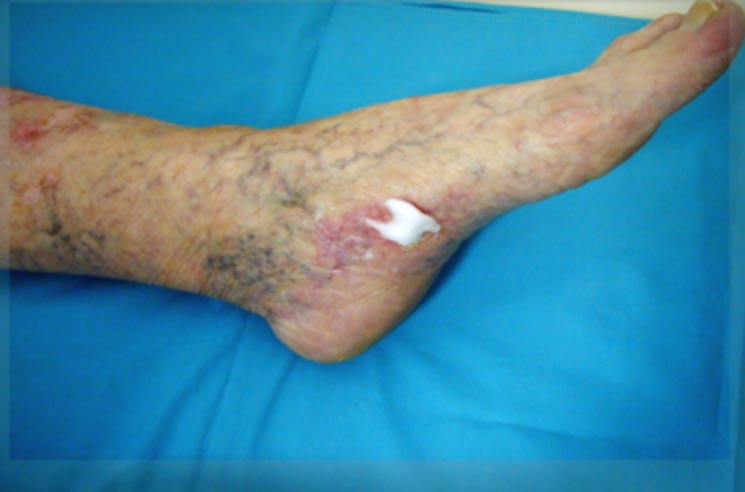

Zahájení léčby a stav po 22 převazech

Zahájení léčby a stav po 22 převazech.